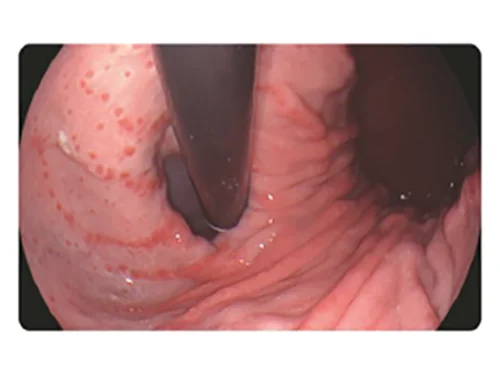

Белый свет

DSI

Белый свет

PSI

Белый свет

TEI